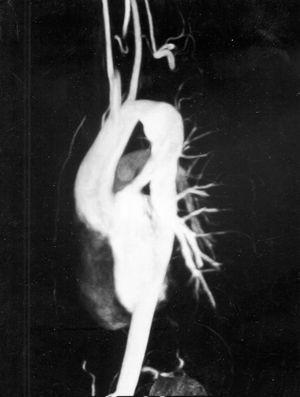

Figura 1. Angiorresonancia tridimensional con gadolinio. Paciente menor de un mes. Proyección coronal oblicua. Coartación extensa con paso de 1-2 mm. Circulación colateral. Flecha + CoA: zona de coartación.